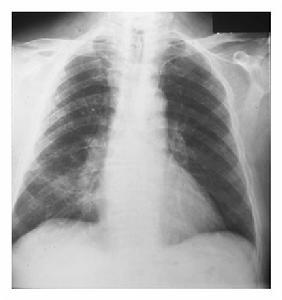

小儿淋巴细胞间质性肺炎(lymphocytic interstitial pneumonia,LIP)为一种肺间质和肺泡腔内成熟淋巴细胞良性增生的不常见病变。由于淋巴细胞间质性肺炎在成人中罕见,但常见于儿童,并多伴AIDS发生。 [1]